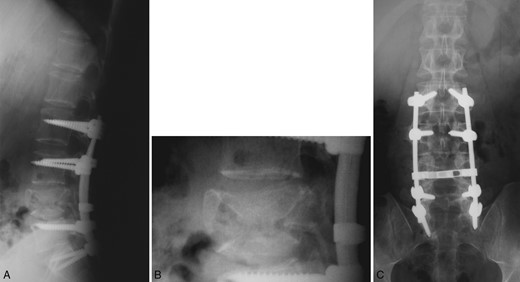

Treatment with biphosphonates and interferon was initiated, which is well tolerated at 18 months following the diagnosis. Over this period, he has not developed any skeletal or extraskeletal signs of the disease. Regular imaging follow-up did not show any instrumentation failure, new vertebral fracture or subsidence and signs of screw loosening (Fig. 3). Soon after surgery, he returned to his normal activities free of pain without any neurological deficits.

Postoperative plain radiograph of the lumbar spine following L2 to S1 posterior instrumention at 15 months. Good bony fusion is documented at the fractured vertebra with no signs of instrumentation failure.